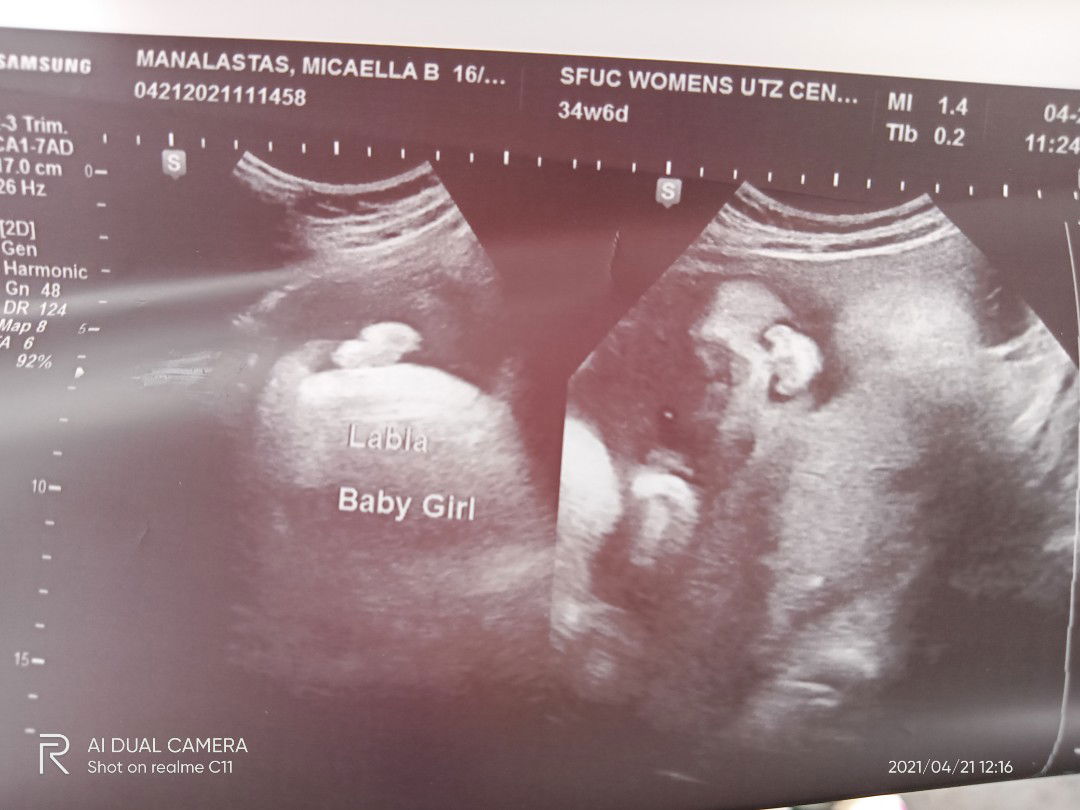

Doc want to induce at 37 weeks cause baby weighed 2kg. Is it ok?

I'm 37weeks now and baby is already 3.4kg. My gynae is letting me to go all the way to 40 weeks without induction. Please discuss with doctor if it's medically necessary to induce.

my baby is 3.3kg when im at 36 weeks. nw doc monitoring the baby wt weekly and will induce if have to. doc worry the baby will b too big for normal del.